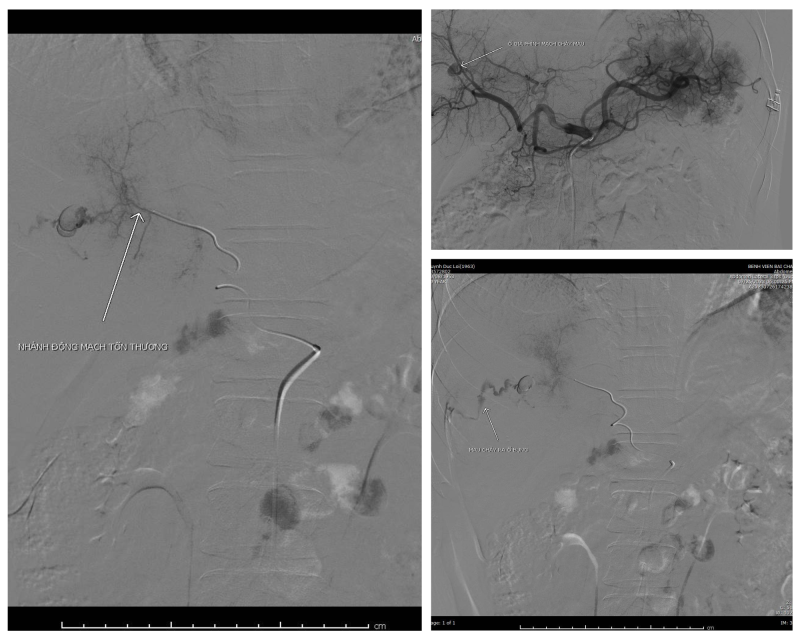

Hình ảnh trước can thiệp

Với hệ thống máy chụp mạch

máu số hóa xóa nền (DSA), kíp can thiệp do Bs.CKI Lê Tiến Hưng, Trưởng Đơn

Nguyên điện quang - can thiệp, Bệnh viện Bãi Cháy đã tiến hành can thiệp nút

mạch thành công cho bệnh nhân sau gần 1 tiếng đồng hồ, giúp cầm máu nhanh chóng

cho bệnh nhân.